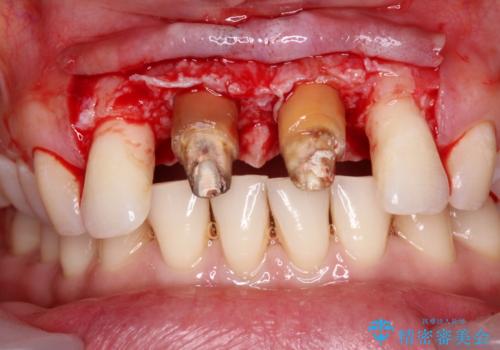

不適合なクラウンが装着されていたため、歯周ポケットが深くなっていましたので、矯正治療前に歯周外科処置を行って歯周ポケットを除去し、矯正治療後にオールセラミッククラウンにて補綴治療を行うこととしました。

- 外科手術のため、術後に痛みや腫れ、違和感を伴います

- 歯周組織再生治療は患者様の状態によって術後の経過が異なります(見た目が改善しない場合もあります)

- 歯周組織再生治療は自費診療(保険適用外)となります